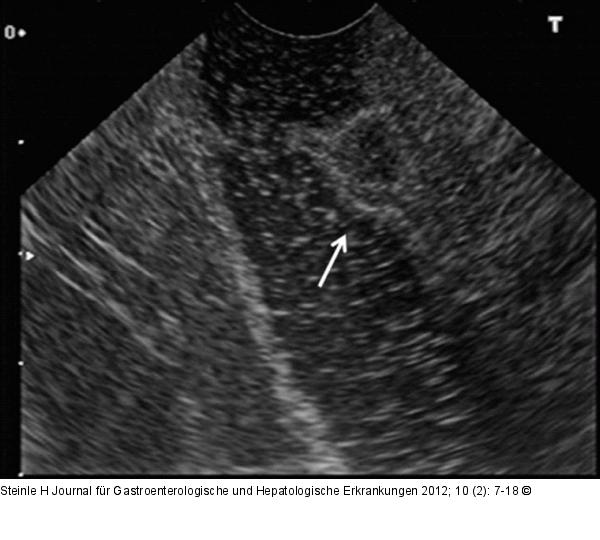

Abbildung 4: Gastrinom - Duodenum

Zirka 7 mm großes Gastrinom im Duodenum (Endosonographie). |